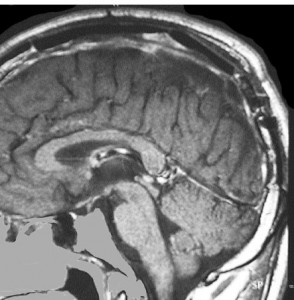

上矢状洞髄膜腫 superior sagittal sinus meningioma

また別な例です。1986年13歳の時に2度の開頭手術を受けましたが,全摘出できずにそのまま経過観察されました。

左の画像は1997年の術前のものです。これを2回に分けて全摘出しました。上矢状洞はやはり冠状縫合のあたりから静脈洞交会まで摘出しました。その下の大脳鎌も全て摘出したので,直静脈洞の上壁を開けることになり,直静脈洞からの激しい出血があり縫合して直静脈洞形成をするのが大変でした。手術後16年が経過しますが再発していませんし,社会人として普通に暮らせています。

この例が教えてくれることは,上矢状静脈洞は全長にわたり切除してしまっても,神経脱落症状を出さないで普通に生きて行かれるということです。